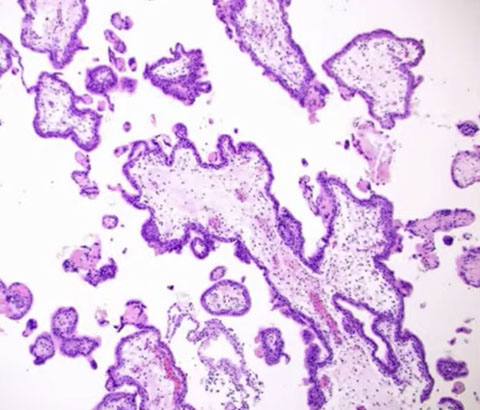

Hydropic Abortus

Presents as missed abortion c declining hCG levels

- grossly tissue scant, fetal parts usually not visible

- villi are uniform, round and occasionally fibrotic

- stromal vessels are rare and nonbranching, can have nRBCs

- trophoblastic hyperplasia is rare, but when present is polar

IHC: (+) p57 villous stromal cells and cytotrophoblasts

Genes: are diploid or aneuploid, occasionally triploid

Px: no inc risk of persistent dz